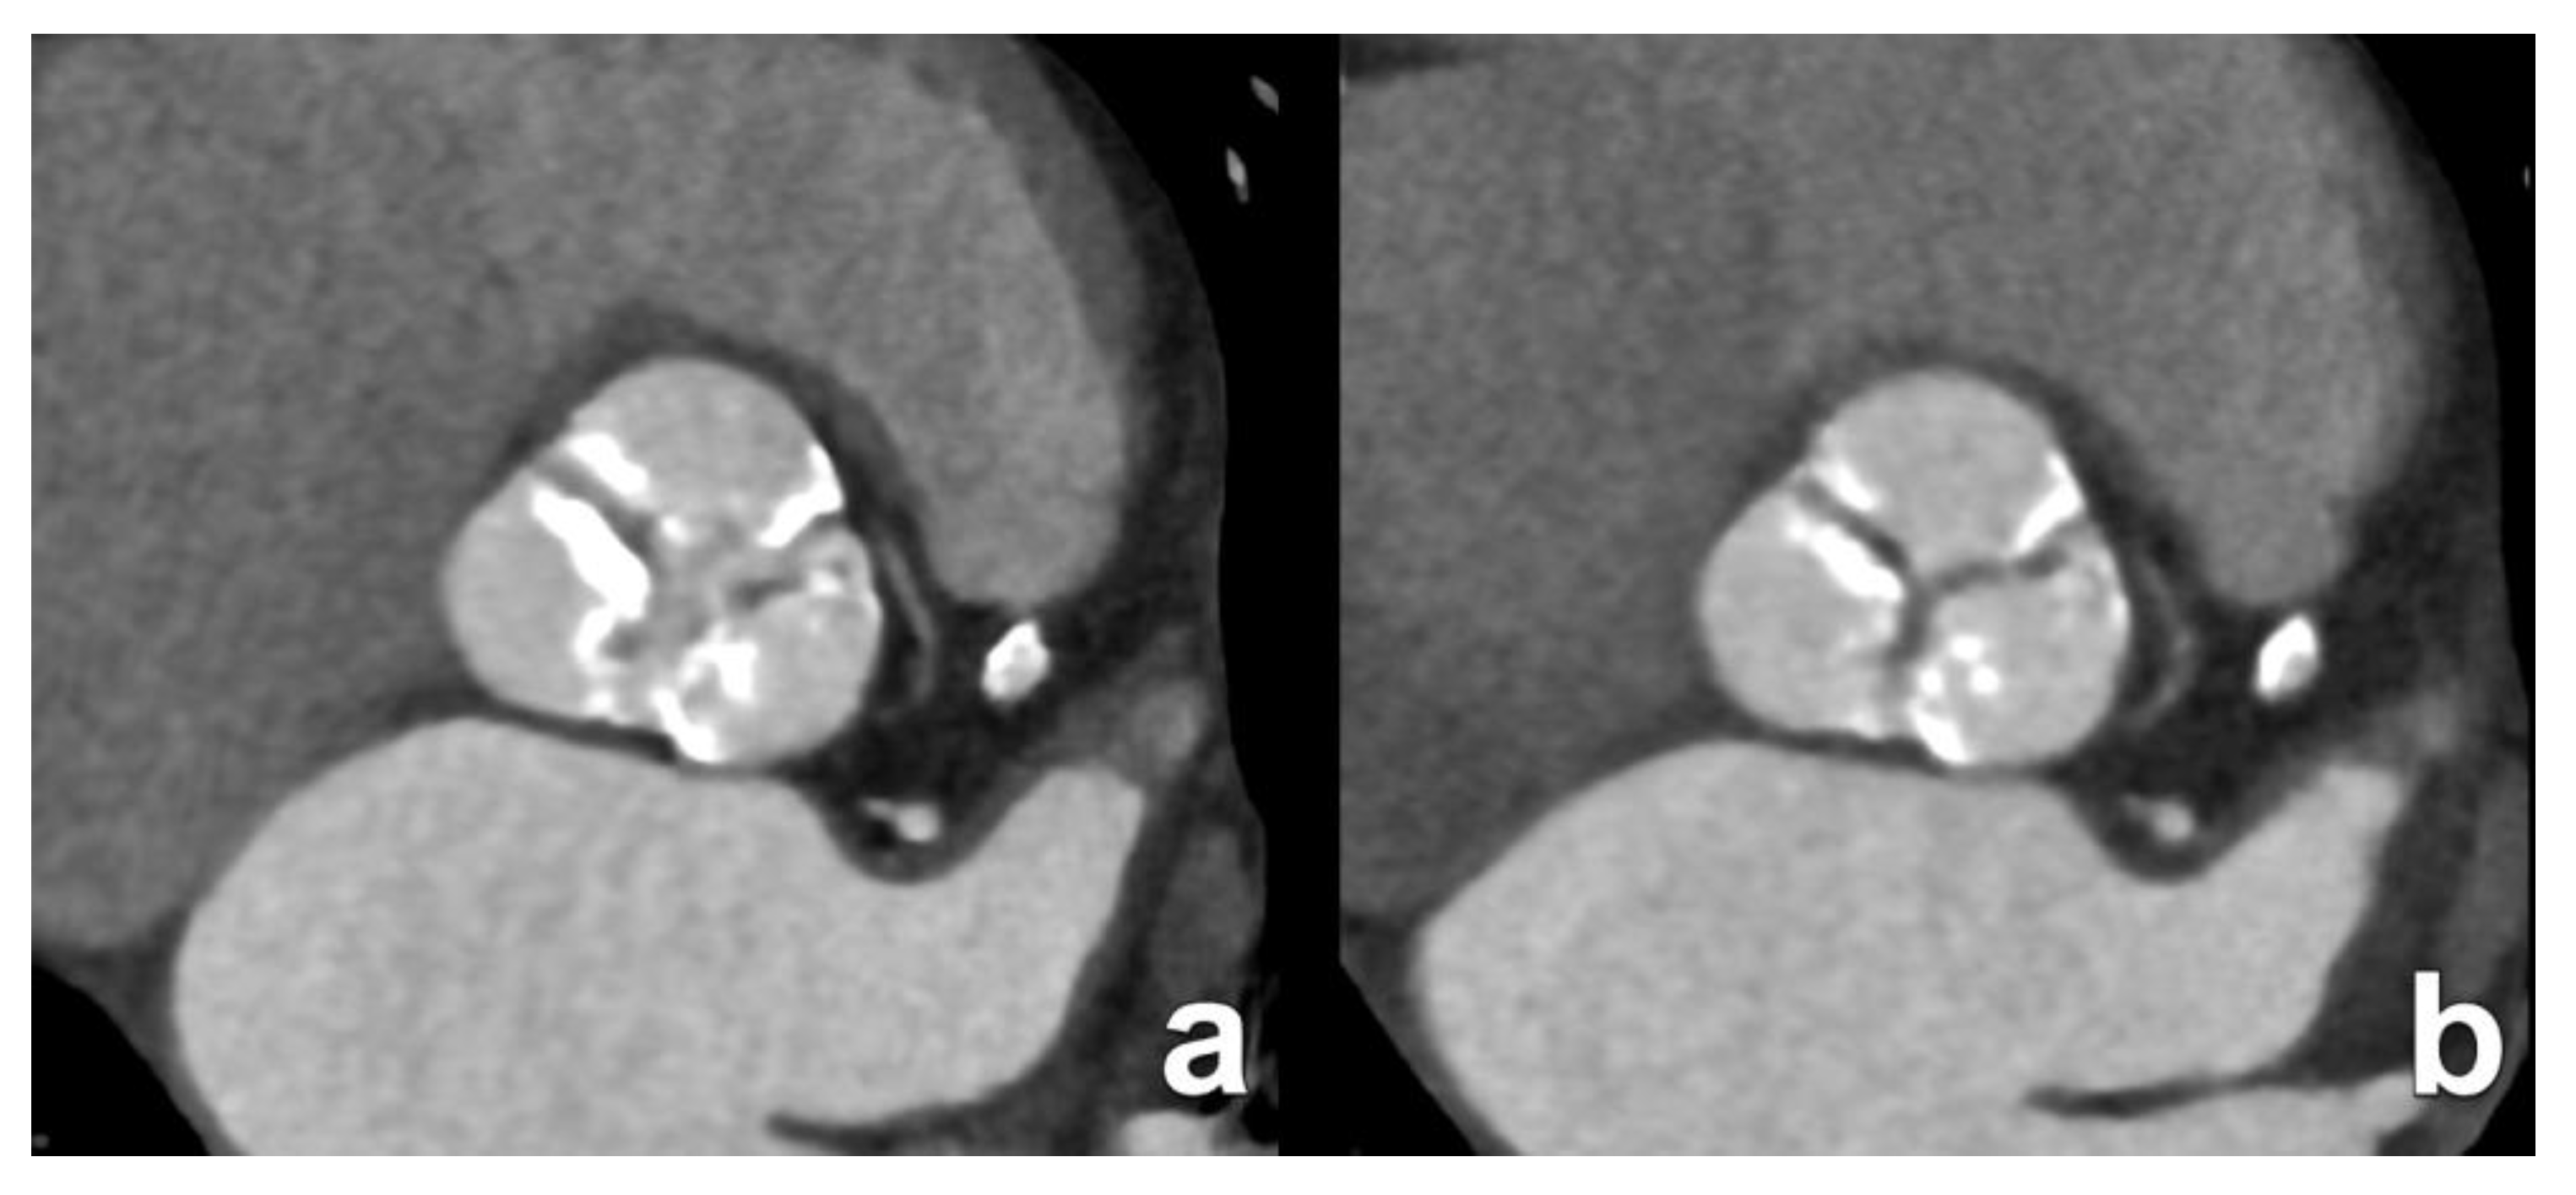

3. Transcatheter Aortic Valve Replacement

- Blanke, P.; Weir-McCall, J.R.; Achenbach, S.; Delgado, V.; Hausleiter, J.; Jilaihawi, H.; Marwan, M.; Nørgaard, B.L.; Piazza, N.; Schoenhagen, P.; et al. Computed tomography imaging in the context of transcatheter aortic valve implantation (TAVI)/transcatheter aortic valve replacement (TAVR): An expert consensus document of the Society of Cardiovascular Computed Tomography. JACC Cardiovasc. Imaging 2019, 13, 1–20. [Google Scholar] [CrossRef]

| Aortic annulus dimensions | Long- and short-axis diameters Area Perimeter | Sizing algorithms are device- and manufacturer-specific. |

| Aortic valve cuspidity | Comment on number of leaflets | The presence of a bicuspid valve may increase procedural complexity and increase the risk for permanent pacemaker implantation after the procedure. |

| Coronary ostia heights | Distance from annular plane to bottom of left and right coronary ostia | As a rule of thumb, a minimum diameter of 10 mm is considered the threshold to avid ostial coronary obstruction by migrated leaflet calcifications. |

| Sinus of Valsalva dimensions | Long- and short-axis cross-sectional diameters Largest cross-sectional diameter Commissure-to-cusp diameter Height of the coronary sinus | The aortic sinus needs to be wide enough to accommodate displaced native leaflet calcifications during the deployment of the THV. |